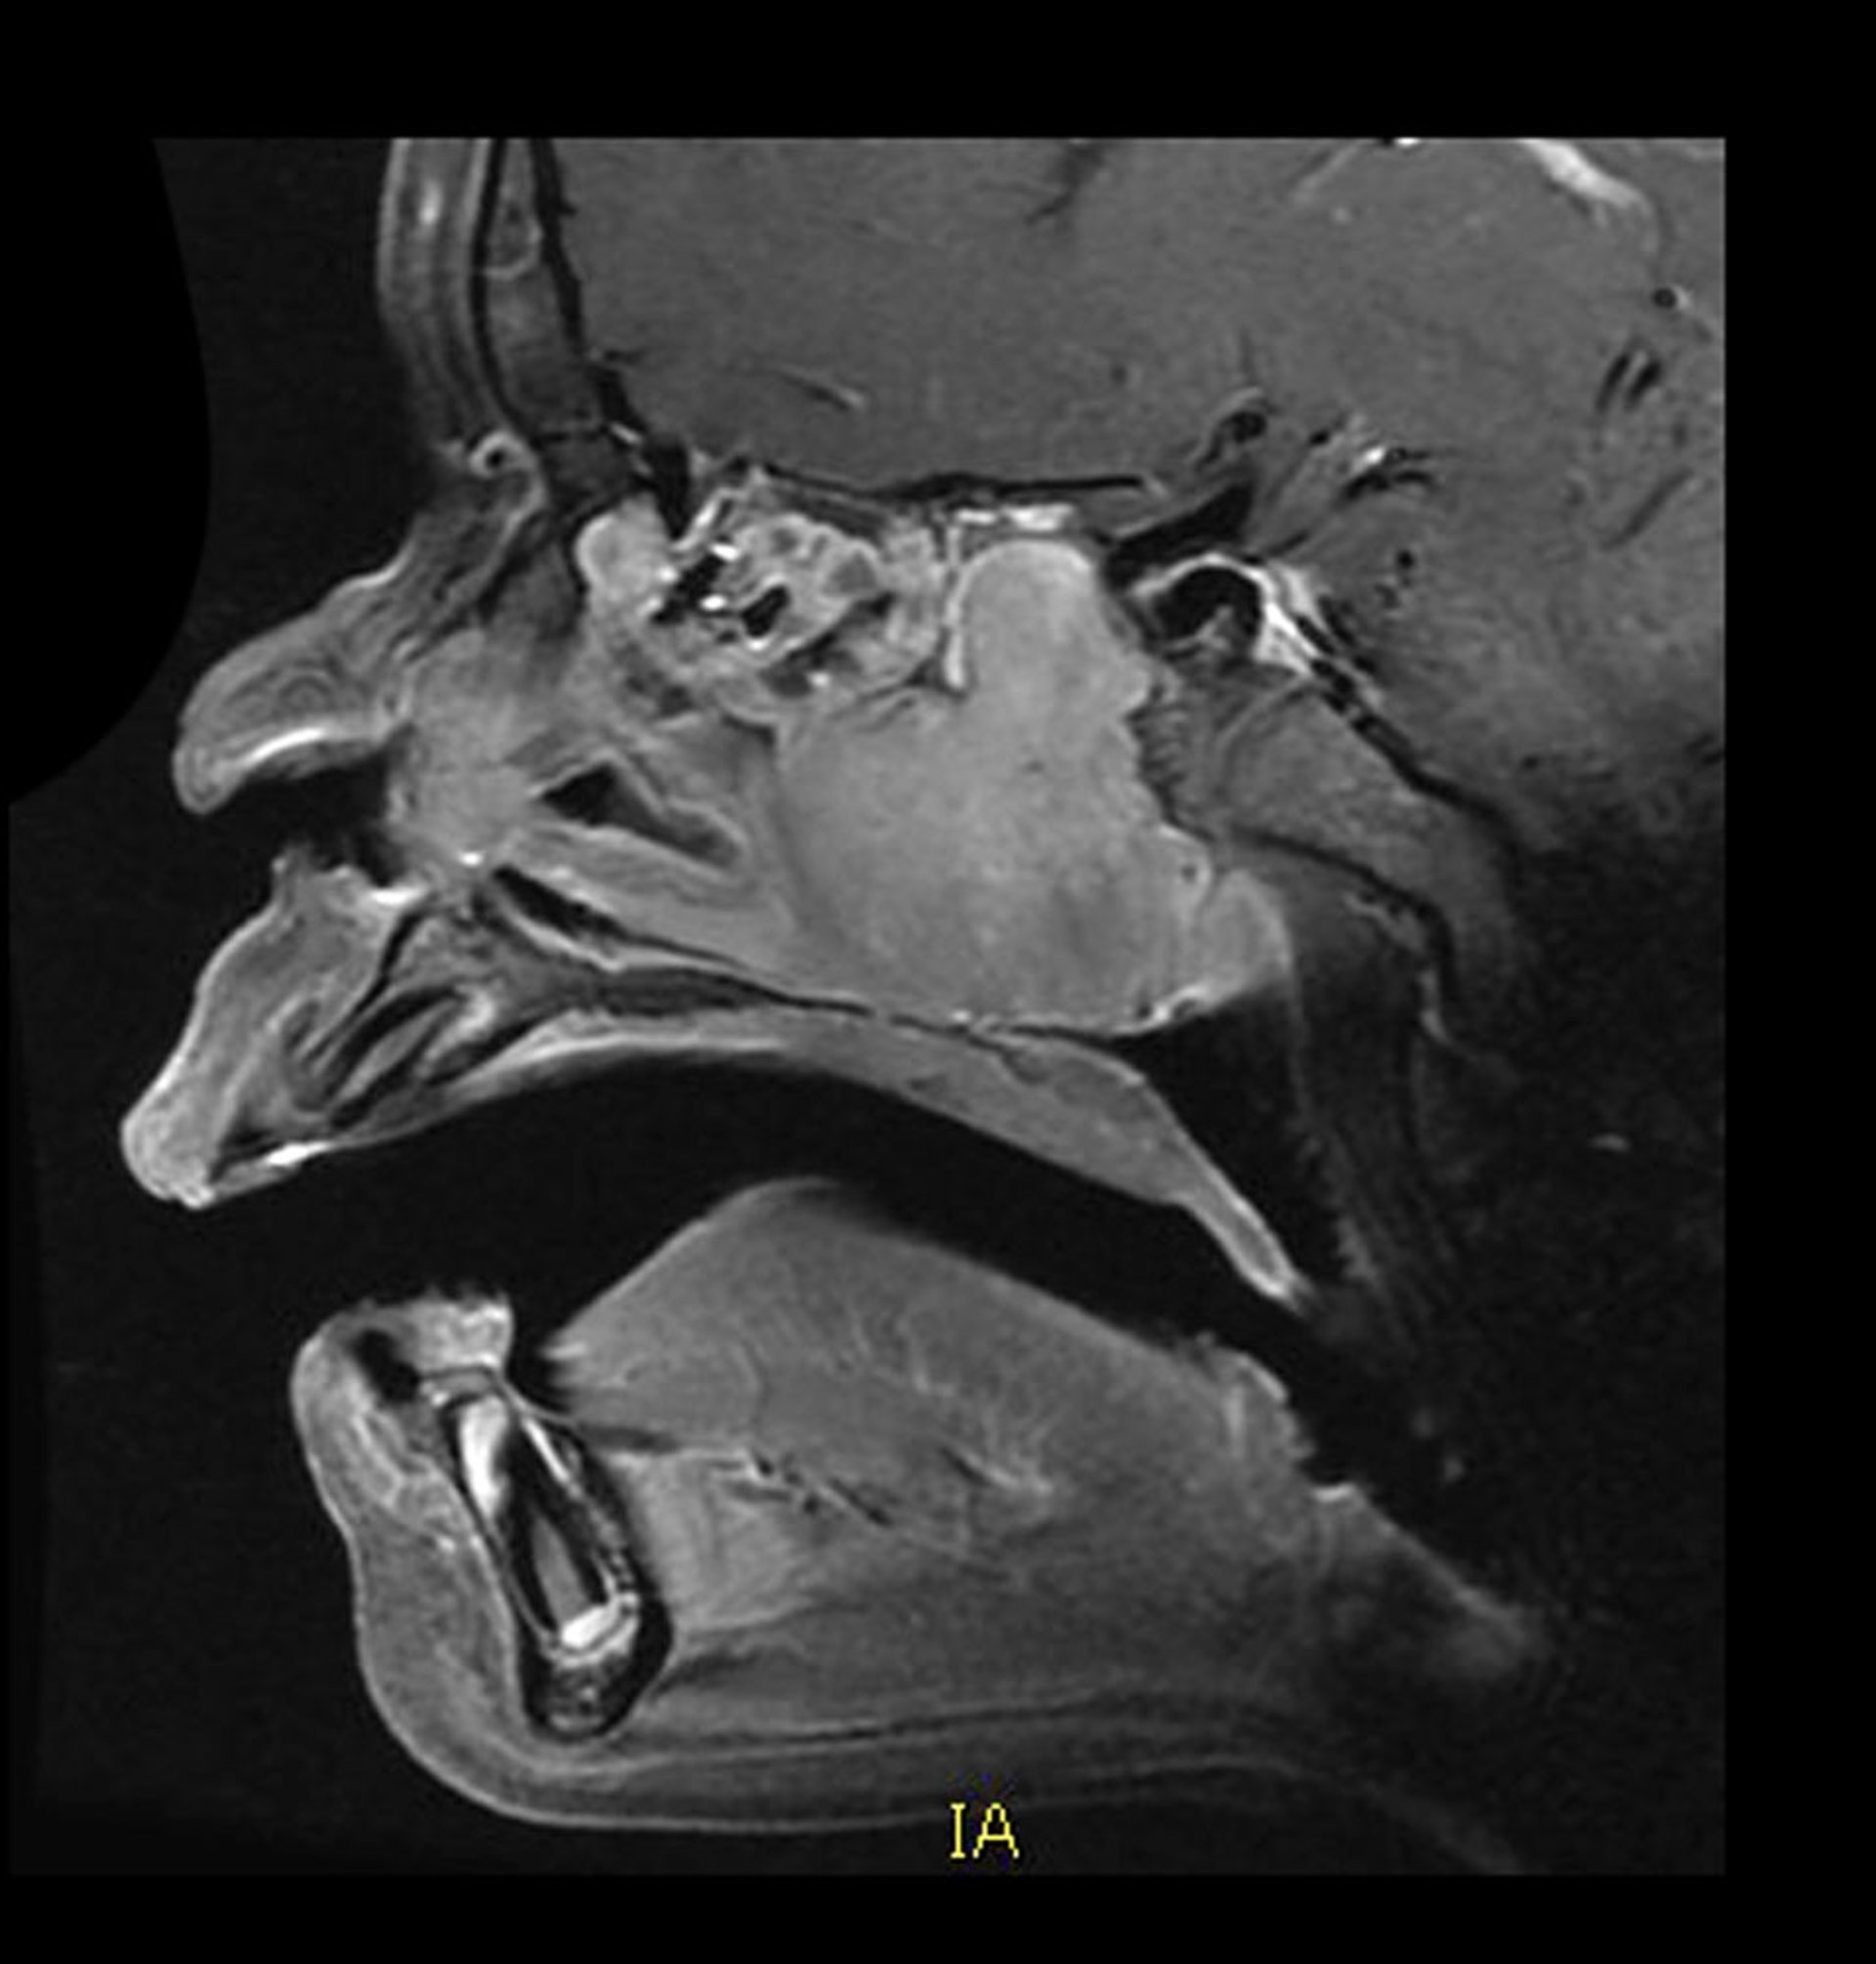

Juvenile Nasopharyngeal Angiofibroma (MRI)

This sagittal, contrast-enhanced MRI shows the typical location and appearance of a vascular juvenile nasopharyngeal angiofibroma. There is a homogeneously enhancing mass in the posterior nasal cavity growing posteriorly into the sphenoid sinus. There is associated bone destruction also.

Living Art Enterprises/SCIENCE PHOTO LIBRARY